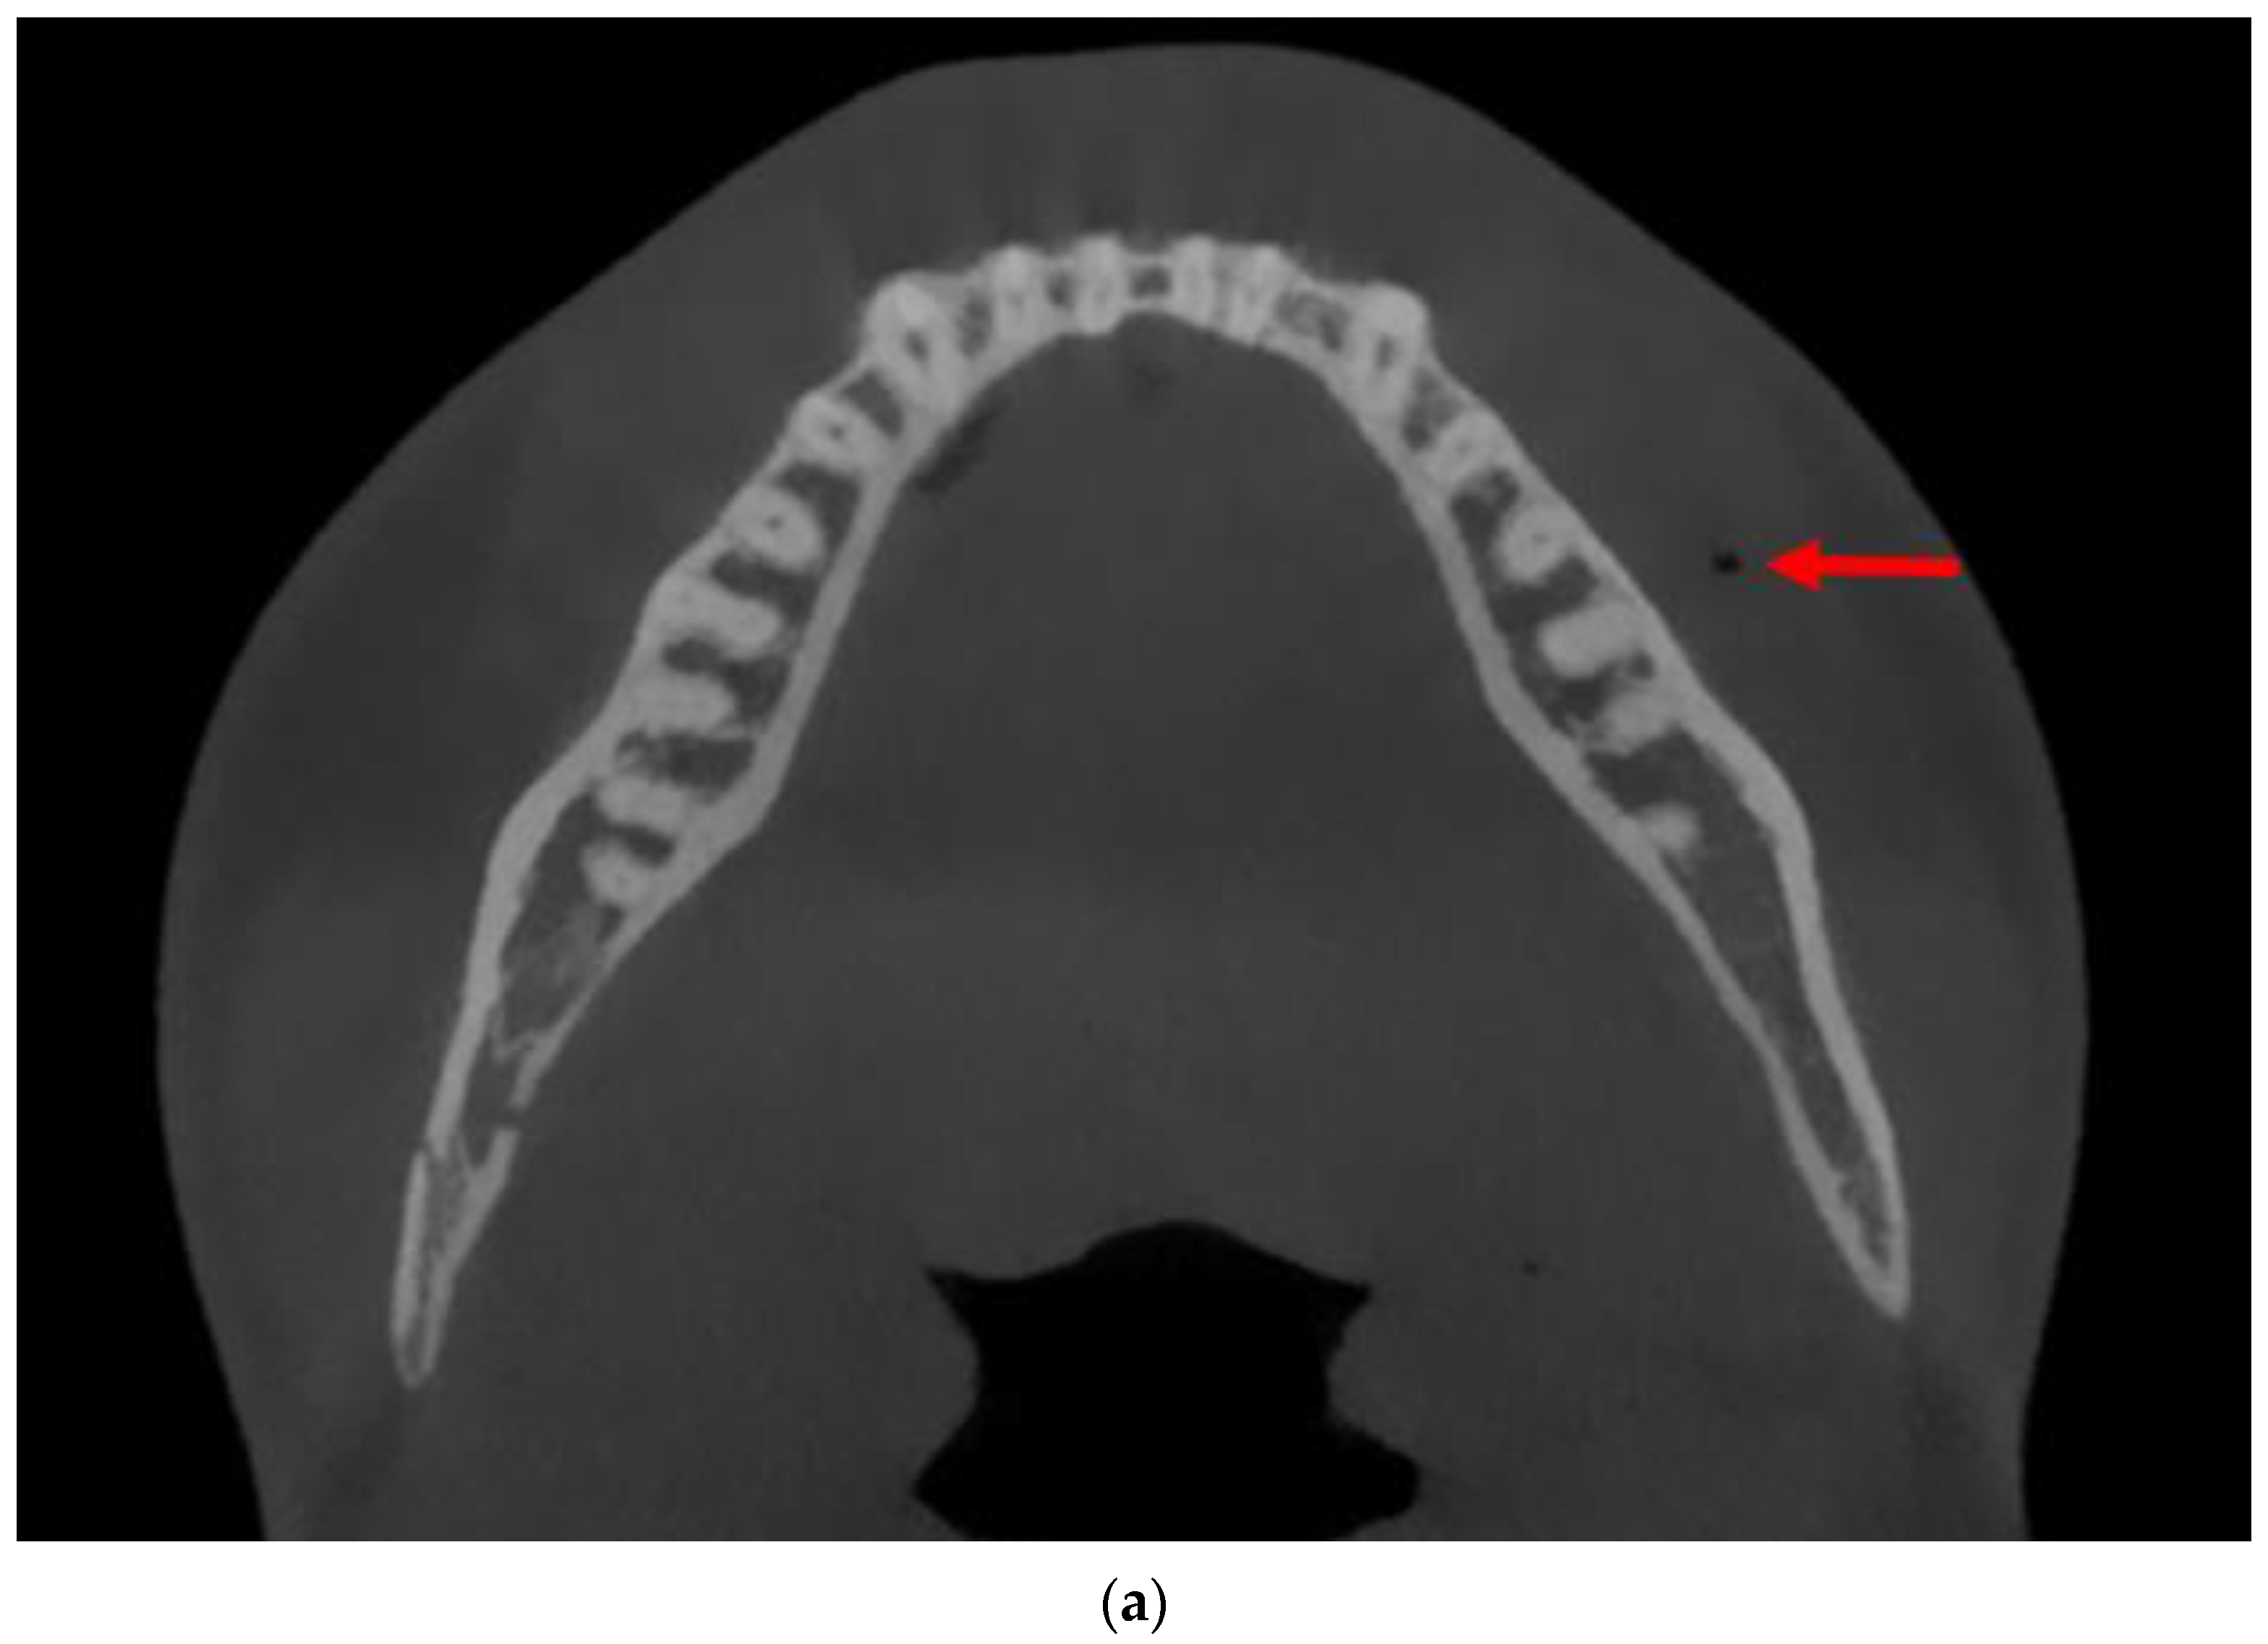

3.3. Case 3

4. Discussion